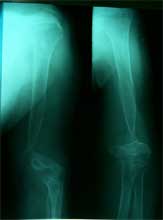

15岁,男。股骨骨母细胞瘤       肿瘤段截,异体骨植骨内固定,术后7年,正常生活。